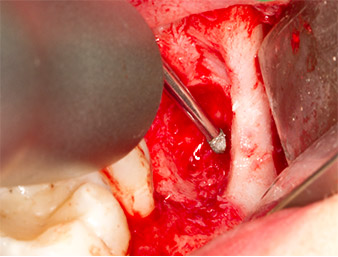

The tissue above the root remnant was not completely ossified and consisted for the most part of granulation tissue modified by inflammation (Fig. 4).

To obtain autogenous material for subsequent wound treatment, healthy bone chips were harvested from the surroundings of the root remnant with a piezo surgical instrument (Piezomed B5) (Fig. 5).

The autogenous tissue was removed with the scraper-shaped section of the working part of the instrument and stored in a physiological saline solution until further use (cf. Fig. 13).